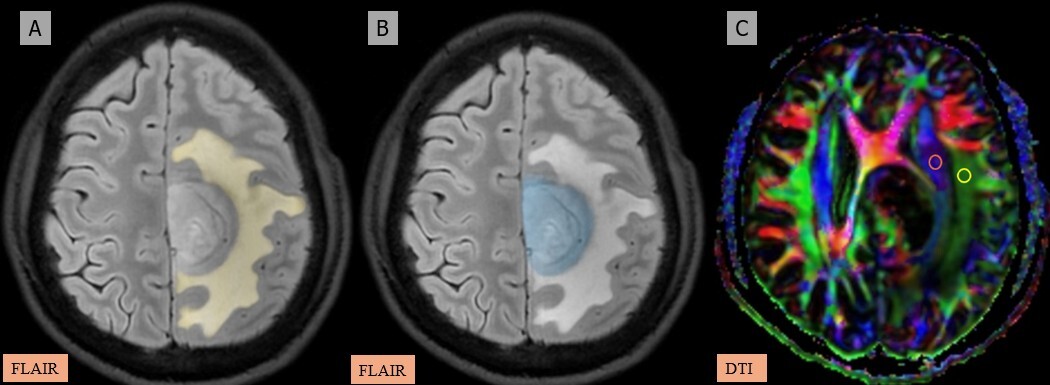

Figure 4

A-C) Patient with a low-grade glioma in the left frontal region presenting with headache and seizures. A) and B) Axial fluid-attenuated inversion recovery (FLAIR) images show the segmented peritumoral oedema (yellow) and tumour volume (blue). C) Image describing the calculation of the diffusion tensor image analysis along the perivascular space (DTI-ALPS) index using two regions of interest (ROIs) drawn within the projection (blue) and association (green) fibres in the left periventricular region